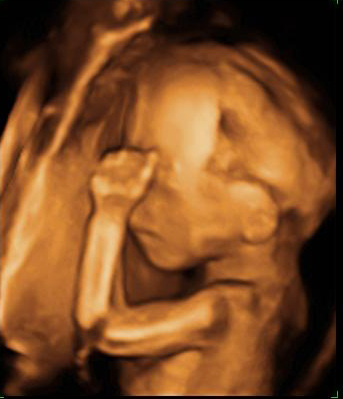

En la ecografía en 4D de un feto de 18 semanas de embarazo se ve la cara ya armonizada: las orejas y los ojos que en un principio estaban desplazados, ya se encuentran en su lugar, lo que le da una imagen mucho más "humana".

Ecografía de la cara de un bebé de 18 semanas

A esta edad temprana, apenas 20 semanas de gestación, las estructuras faciales básicas están prácticamente conformadas.